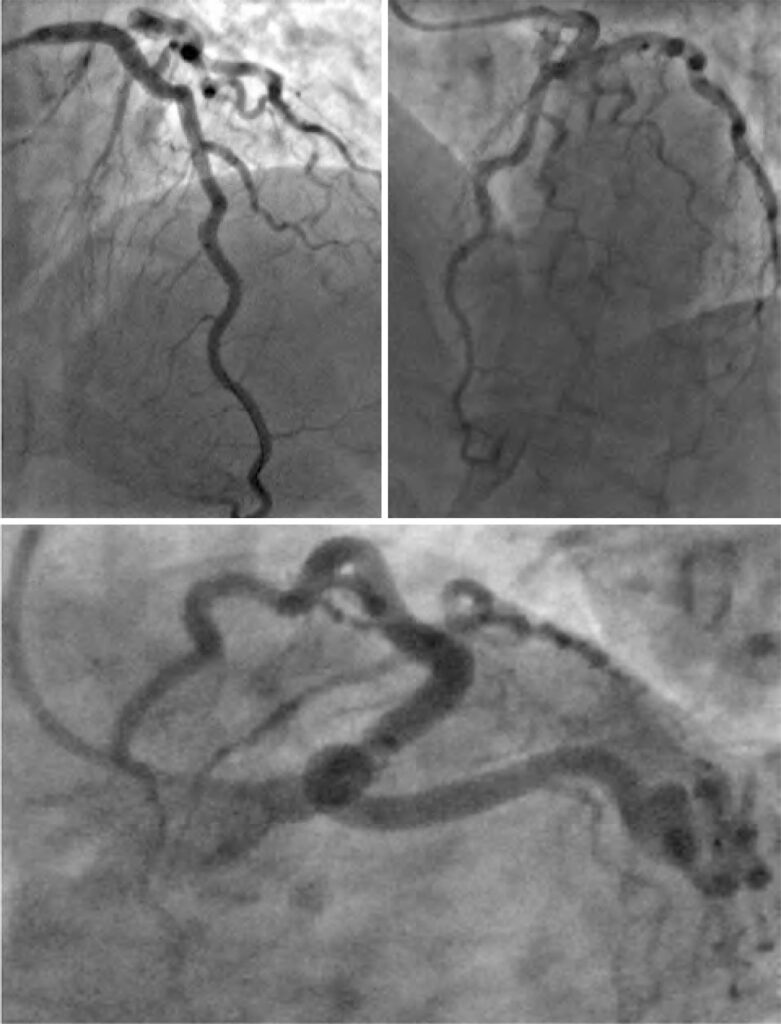

A dissecção espontânea da artéria coronária é definida como uma dissecção coronária epicárdica não iatrogênica, não associada à aterosclerose ou a trauma. A lesão miocárdica ocorre devido à obstrução da artéria coronária causada por hematoma intramural ou ruptura da íntima, em vez de ruptura de placa aterosclerótica ou trombo intraluminal. Relatamos um caso de dissecção espontânea tipo 2 variante A no segmento médio da artéria descendente anterior apresentando-se como síndrome de Wellens tipo A, que necessitou de intervenção coronária percutânea para alívio de angina refratária e congestão pulmonar.